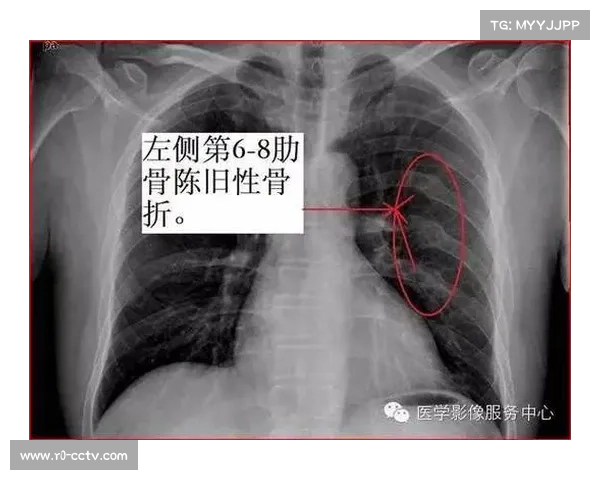

肋骨骨折在足球运动中并不少见,尤其是发生在激烈对抗中的头球或身体碰撞时。对于霍夫曼而言,这次骨折并非普通的肋骨裂伤,而是涉及了多根肋骨的复杂骨折。医生表示,虽然肋骨本身并非致命伤害,但由于肋骨周围紧邻肺部,任何细微的伤害都可能影响到呼吸系统的正常功能。

此外,霍夫曼的肺部伤情更为严重,这意味着他的呼吸可能会受到直接影响。通常情况下,肋骨骨折后若不及时处理,可能会导致肺部出现破裂、气胸等并发症,危及球员的生命安全。霍夫曼的伤情也没有例外,早期检查发现,他的肺部已有部分压迫性损伤,必须立即通过医疗干预来防止情况恶化。